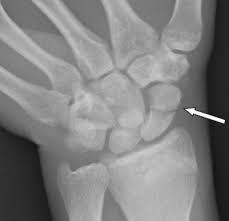

Scaphoid fractures are a type of broken wrist. They happen when you break your scaphoid bone — a small bone near the base of your thumb. Your scaphoid is one of your carpal bones, the collection of bones that makes up your wrist. Scaphoid fractures are almost always caused by catching yourself with outstretched arms after a fall. Car accidents and other traumas can also cause them. You might need surgery to repair your bone. Most people need around three months to recover from a scaphoid fracture.